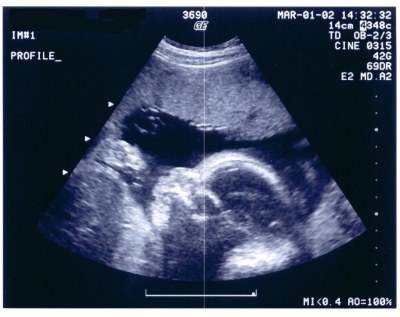

این روزها دستورالعمل حذف غربالگری جنین که از سوی وزرات بهداشت اعلام شده، خبرساز شده است.

مستوره برادران نصیری: دستورالعمل حذف غربالگری جنین

از سوی وزارت بهداشت اعلام شده است، این موضوع باعث بحث و چالشهای زیادی

شده خصوصا که این موضوع میتواند تولد نوزادانی با احتمال بیماریهای خاص و